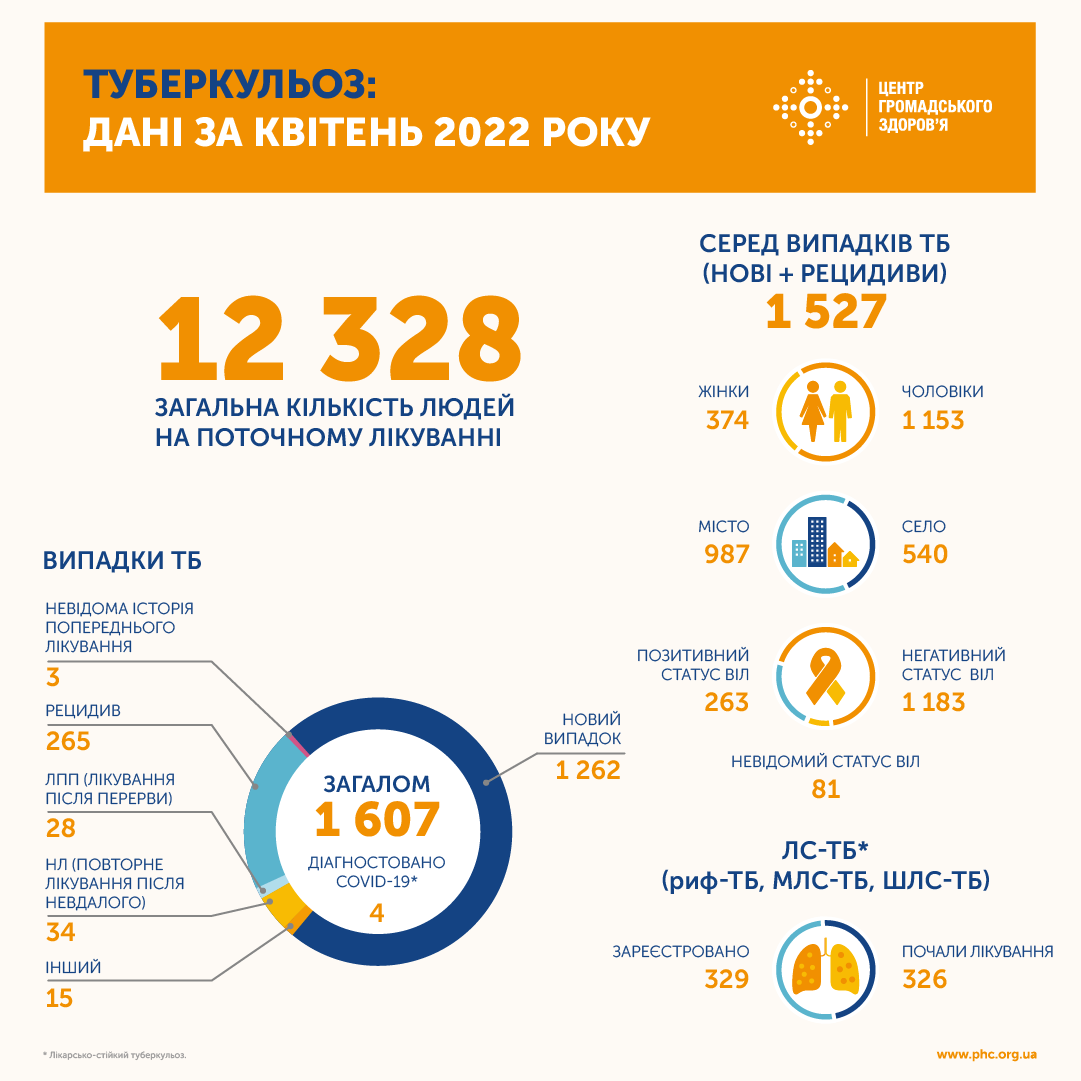

В апреле текущего года в Украине зарегистрировали 1522 случая туберкулеза.

Всего в апреле этого года, как пишет ЦОЗ, от туберкулеза лечились 12 540 человек.